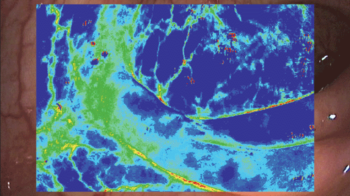

CHb Enhancement

Судас болон салст бүрхэвчийн гэрлийн ойлт, шингээлтийн спектрийн ялгаанд тулгуурласан алгоритм нь гемоглобины агууламжийг өнгөөр дүрслэн харуулдаг. Ингэснээр бичил судасны гемоглобиныг (CHb) тодруулан харах боломжтой болно. Гемоглобины дүрслэл сайжирснаар эмгэг өөрчлөлтийг илүү нарийвчлалтай оношлох боломжтой бөгөөд ялангуяа үрэвсэлт үйл явцыг илрүүлэхэд хялбар болгодог.

Улаан болон шар өнгөөр будагдсан хэсгүүд нь судасны баялаг бүхий бүтэцтэйг илтгэнэ. Энэ нь халдвар, цус алдалттай гастрит эсвэл хавдар байж болзошгүйг илрүүлдэг.

-

Хөх өнгөөр будагдсан хэсгүүд нь судас багатайг илэрхийлнэ. Энэ нь эдийн хатингаршил, эсвэл хатингаршлын гастриттай холбоотой байж болно.